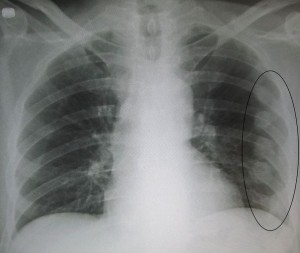

Диагностика и лечение

Перед тем как начать лечение перелома грудины, необходимо пройти неоднократное обследование, которое должно определить не только тип, но и степень тяжести травмы. Благодаря тщательному обследованию, можно выявить возможные повреждения внутренних органов. Как и при других видах перелома, обязательно необходимо сделать несколько видов рентгена для того, чтобы получить точный результат. Самые точные и достоверные исследования рекомендуется сделать при помощи компьютерной томографии.

Лечение переломов грудной клетки и грудины должно осуществляться только после того, как будет поставлен точный диагноз. Кроме того, необходимо убедится в том, что кости скелета, а также внутренние органы не пострадали. Лечащий доктор должен назначить несколько рентгенологических исследований для того, чтобы выяснить состояние грудины, ребер и других органов. Необходимо обязательно сделать боковые снимки грудной клетки для того, чтобы определить смещение отломков кости.